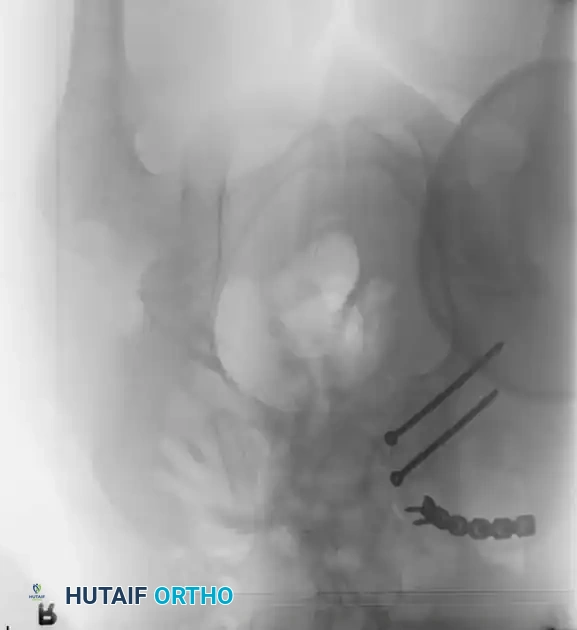

3. Percutaneous Sacroiliac (SI) Screws (Posterior Ring)

The gold standard for posterior ring fixation in appropriately selected patients.

* Indications: Sacral fractures, SI joint disruptions, crescent fractures.

* Technique: Performed under strict fluoroscopic guidance (Inlet, Outlet, and Lateral sacral views).

* Trajectory: The guide wire is advanced from the lateral ilium, across the SI joint, into the S1 (or S2) vertebral body.

* Safety Corridors: The surgeon must possess an intimate understanding of sacral dysmorphism. The "safe zone" is bounded by the sacral neural foramina inferiorly, the spinal canal posteriorly, and the sacral ala anteriorly.

Pitfall: Failure to recognize a dysmorphic sacrum (characterized by upper sacral segment elevation, non-recessed alae, and oblique neural foramina) can lead to catastrophic L5 nerve root injury or vascular penetration during SI screw placement.

Image